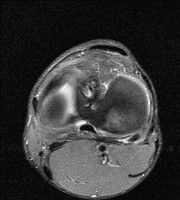

무릎 mri 간단히 봐주실 수 있으시나요 ㅠㅠ

안녕하세요 8년전 십자인대 수술하고 최근 무리한 운동에 무릎 불편감이 생겨서

mri 찍었습니다.

진단결과는 첫 찍은 병원에서 활액막염 이라는 진단을 받았습니다. 혹시 봐주실 수 있으실까요?

올라온 MRI가 단편적이라서 정확한 진단에 어려움이 있지만 십자인대에는 큰 이상이 있지는 않은것 같으며, 무릎관절내 물이 있는 것으로 보아 활액막염의 진단이 맞을 것 같습니다.

하지만 단편적인 영상이기 때문에 촬영병원에서 정확한 판독지 등을 받으시는 것이 좋겠습니다.